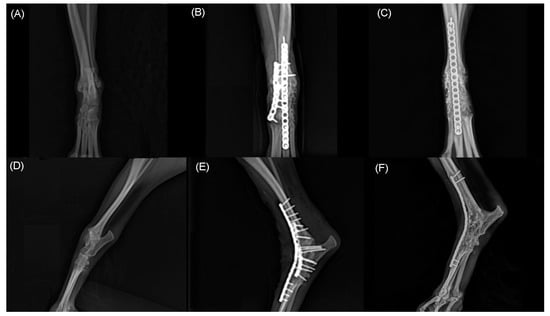

Figure 5. Craniocaudal (A,B,C) and mediolateral (D,E,F) radiographs of right tarsal joint. Note hyperextension of tarsal joint before surgery (A,D). Immediate postoperative radiographs (B,E) shows pantarsal arthrodesis performed using double 1.2 mm locking plate place on dorsally. At 21 months postoperative radiographs shows complete bony union and remodeling (C,F).

Two months after the initial surgery, there was no improvement in neurological symptoms despite rehabilitation treatment. Thus, surgical treatment was decided after consulting with the owner. The dog was premedicated with intravenous (IV) administration of hydromorphone (0.05 mg/kg) and midazolam (0.2 mg/kg). Cefazolin sodium (22 mg/kg IV) was used as a prophylactic antibiotic before surgery and was injected additionally every 90 min during surgery. General anesthesia was induced with propofol (2–4 mg/kg IV) and maintained with inhaled isoflurane and oxygen. Analgesia was provided by constant rate infusion (CRI) of remifentanil (0.1–0.3 μg/kg/min). Greater trochanteric osteotomy was performed to secure the field of view. Proliferated bone on the femoral neck was removed using a high-speed burr. Grossly, the sciatic nerve was ruptured completely and entrapped within fibrotic tissues. The dog was diagnosed with sciatic nerve neurotmesis in combination with preoperative examinations. Each end of the ruptured sciatic nerve was debrided for relieving tension. The size of the defect was measured as 20 mm using a ruler intraoperatively. The nerve ends were mobilized and tension was evaluated during the apposition of both nerve ends. The epineurium was circumferentially exposed by carefully pushing back the mesoneurium with Dumont forceps, and the neurorrhaphy was performed with 7-0 polydioxanone suture (PDS II, Ethicon, NJ, USA) through the epineural suture pattern (Figure 3). While proceeding with the epineural suture, placing the stitches on other than epineurium was avoided as possible. Initially, two simple epineural sutures were placed on medial and lateral sides, 180 degrees from one another. These sutures were not tied until other sutures are placed. Two additional sutures were placed on the cranial and caudal surface respectively and then all sutures were tied. The greater trochanter was reattached using a tension-band wire, and the surgical wound was closed as usual. The debrided fibrotic tissues between both proximal and distal ends of the sciatic nerve with a small amount of remaining nerve tissue were submitted for histopathologic examination, and the composition of the debrided tissue was identified as multifocal axonal degeneration, hemorrhage, and suture granulomas (Figure 4). Cefazolin sodium (22 mg/kg IV twice daily) was prescribed for seven days after surgery. Postoperatively, remifentanil (0.1 µg/kg/min CRI) was administered during the first 12 h and subsequently replaced with meloxicam (0.2 mg/kg subcutaneously once daily on day 1, 0.1 mg/kg orally once daily on days 2–5). Gabapentin (15 mg/kg orally twice daily) was prescribed for alleviating neuropathic pain. A soft padded bandage was applied for 24 h to prevent postoperative edema. At five days postoperatively, passive range of motion exercises (PROM), toe touching and leash walking for 5 min twice daily, and laser therapy and acupuncture twice a week were started as rehabilitation until three weeks after surgery. At three weeks postoperatively, the superficial pain perception from the cranial part up to the proximal quarter below the tarsus was recovered, and the dog was able to ambulate with intermittent knuckling. The dog showed improved proprioceptive, postural reaction and withdrawal reflex. The dog discharged with client education for PROM and toe touching twice daily at home and laser treatment, underwater treadmill and acupuncture were performed twice a week for seven weeks. At seven weeks postoperatively, superficial pain perception was present in the cranial part of the distal tarsal region. At ten weeks postoperatively, the dog was able to ambulate without knuckling, and the superficial pain perception was present, but tarsal joint hyperextension did not improve due to ankylosis. Finally, right tarsal arthrodesis was performed using double 1.2 mm titanium locking plates (Arixvet, Jeil Medical Corp., Seoul, Korea) placed on the dorsal surface of the tarsal joint with rhBMP-2 (Novosis, CGBIO, Seongnam, Korea) three months after the surgery (Figure 5). One of these locking plates and multiple screws were destabilized 7 months after tarsal arthrodesis and bony union was observed without any complications until last follow up.